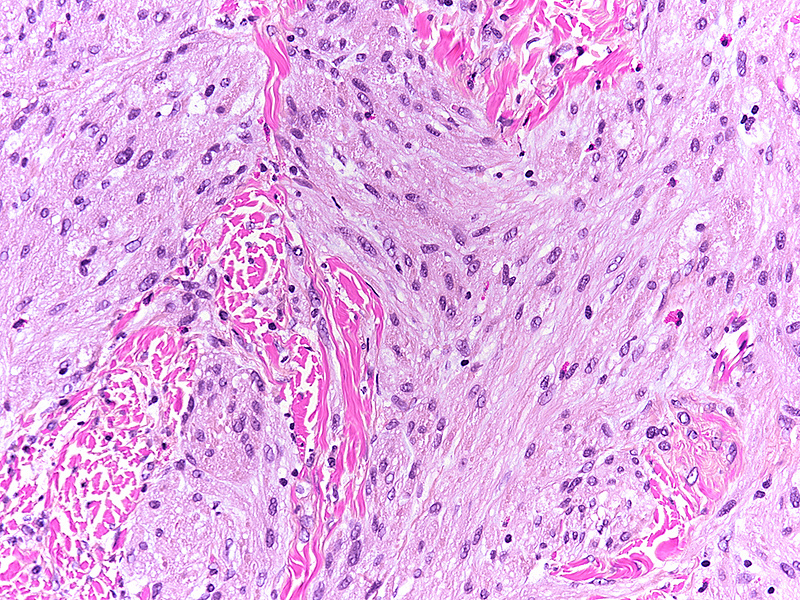

Histologically, we saw a submucosal proliferation of solid nests and ribbons of round to polyhedral cells, measuring approximately 6 mm in largest diameter (Panels A-B). The neoplastic cells generally contained small, uniform nuclei with inconspicuous nucleoli and abundant granular eosinophilic cytoplasm. They were separated by fibrous septa, which contained few inflammatory cells, mostly lymphocytes and few eosinophils (Panel C). In some areas, the neoplastic cells demonstrated cell spindling, still keeping the cytoplasmic features described above (Panel D). The lesion was ill-defined at the base, showing an infiltrative pattern into the surrounding adipose tissue within the submucosal layer (Panels E-F). The neoplastic cells were positive for PAS and strongly immunoreactive for S100-protein (Panels G-H), yet negative for keratin, CD117, DOG-1, and muscle markers, prompting final diagnosis of colonic granular cell tumour.